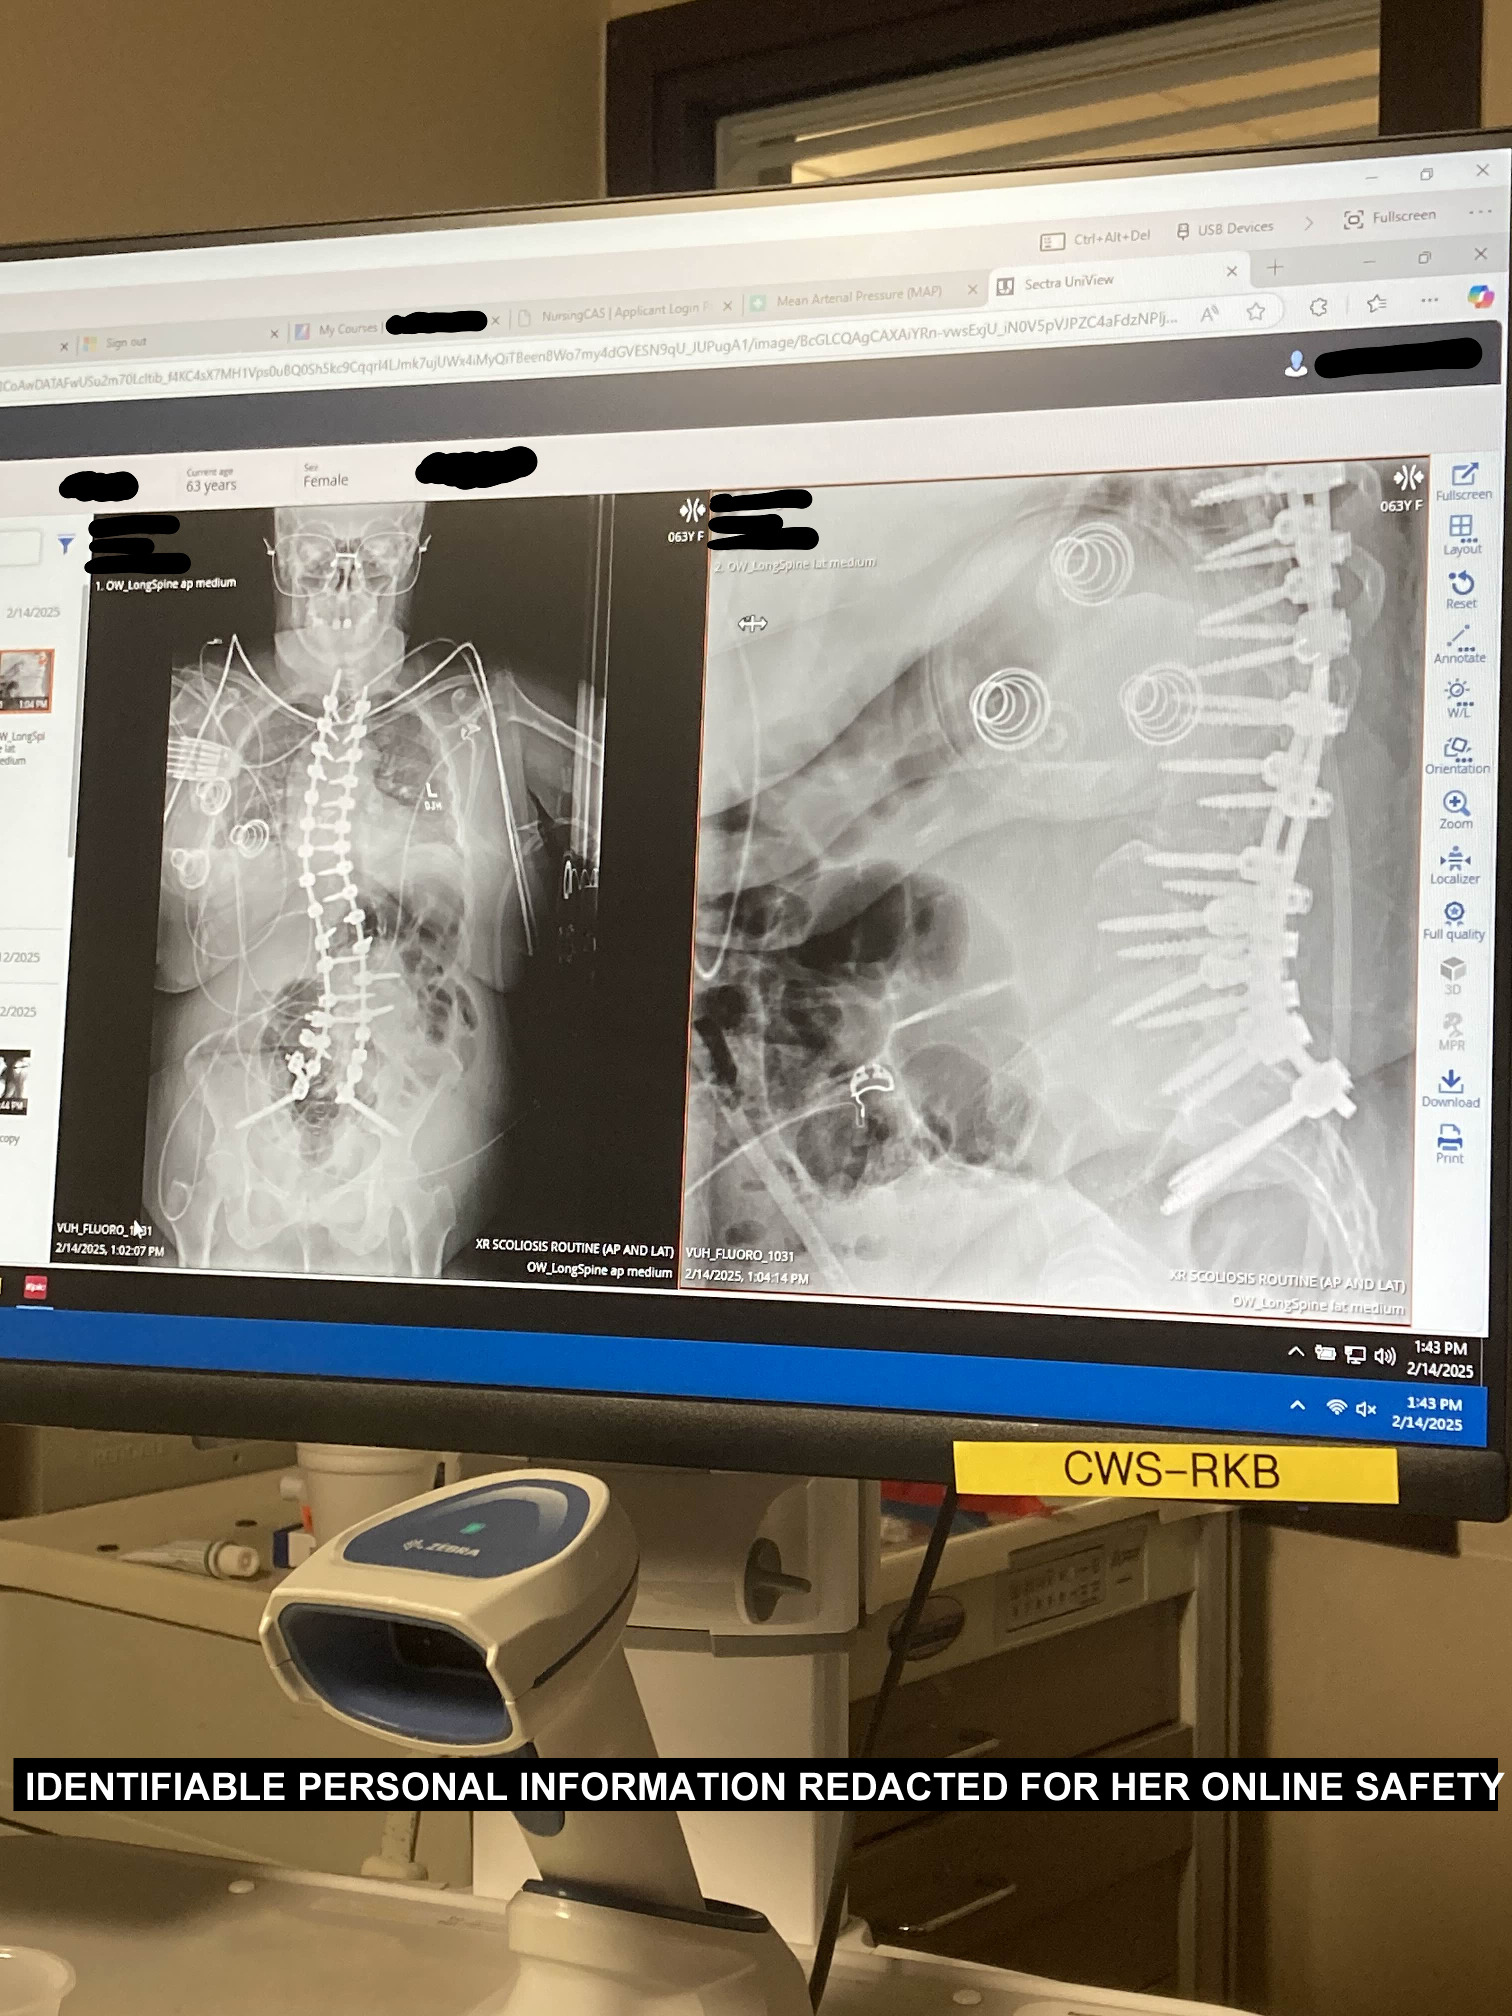

After multiple emergency moves due to landlords wrongfully evicting us just to jack up the monthly rent (as well as obviously refusing to return our deposits), my mother's spinal fusion surgery in early 2025 and the intensive recovery period after getting her fired from her job (that had promised to keep her on despite the surgery), my grandmother's passing the day my mother was supposed to return home from the hospital and the rift that tore through the family, my mother's disability being taken away immediately after her surgery (because apparently an emergency spinal fusion done to keep her organs from being pushed out of place and her spine from twisting so bad, she'd be wheelchair-bound within a few years actually cures extreme scoliosis! i never would've guessed the paper-pushers behind a desk would know so much about medical needs), we've reached a complete breaking point. Bills piled up, loans were taken out, every desperate measure taken just to try to make rent. Every month is a struggle and a choice between what utility we can manage without until either her social security check comes in or food stamps alleviate a bit of the issue.